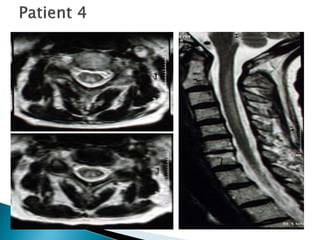

■ 46 F

■ Numb/tingling fingers/toes

■ Unsteady gait

■ PE

◦ Motor normal except HF-4

◦ Dec LT/PP/distally

◦ Vib/prop absent toes/ankles

◦ DTR – Bic/knees 3 – ankles - 0

 + Hoffman’s; toes – ext RT

◦ Gait – ataxic, poor tandem

What neuropathy pattern is this?

a) Symmetric proximal and distal weakness with sensory

loss

b) Symmetric distal sensory loss with or without weakness

c) Symmetric sensory loss with or without distal weakness

and upper motor neuron signs

d) Asymmetric proprioceptive loss without weakness

e) Symmetric weakness without sensory loss

Answer: c. Symmetric sensory loss with or without distal

weakness and upper motor neurons signs.

■ B12 – 115

■ WBC – 1,200

■ Hg – 7.71/ Hct 25/ MCV 108

■ Rx – B12 injections monthly